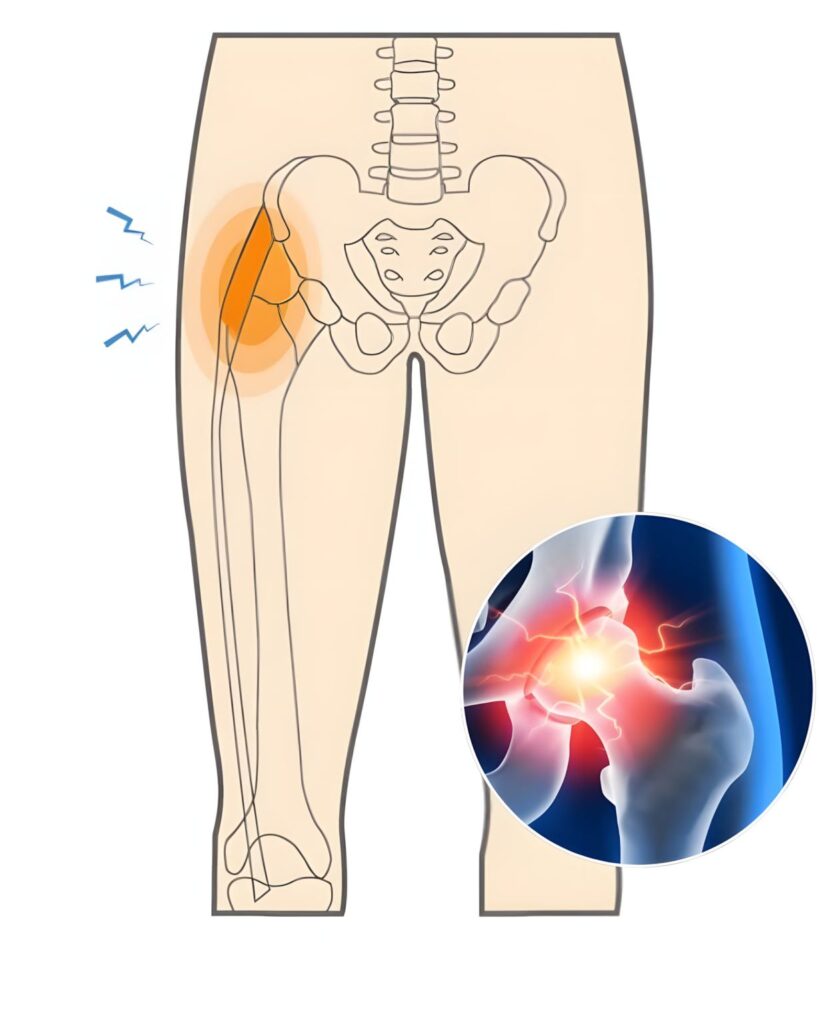

Wanneer er sprake is van slijtage aan de heup, denkt men vaak dat de pijn zich direct in het heupgebied bevindt. Toch ervaren veel mensen de klachten juist in de liesstreek. Dit komt doordat de zenuwen en spieren rondom de heup uitstralende pijn veroorzaken. Het verwarrende is dat deze pijn soms ook doorloopt naar het bovenbeen of de bil, waardoor mensen in eerste instantie denken dat er sprake is van een spierblessure of een rugprobleem.

Het herkennen van liespijn als mogelijk symptoom van heupslijtage is belangrijk, omdat het vaak het eerste serieuze signaal is dat er iets misgaat in het gewricht.